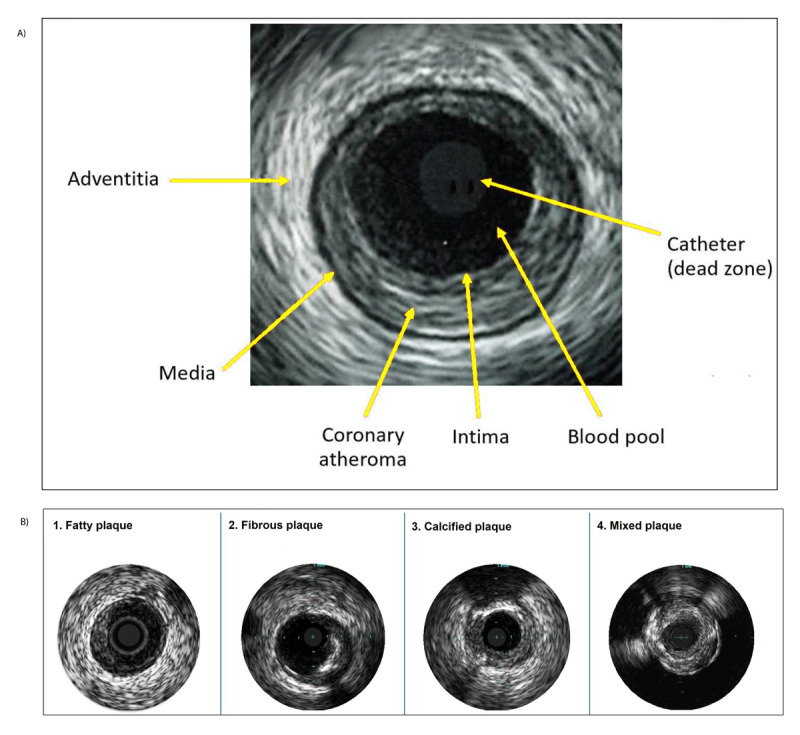

Intravascular ultrasound (IVUS) has significantly advanced the field of percutaneous coronary intervention (PCI), offering enhanced visualization and assessment capabilities that surpass traditional angiography. IVUS technology generates images from reflected ultrasound waves, providing critical insights into plaque characteristics, vessel size, and lesion morphology. These capabilities facilitate precise stent placement, optimal sizing, and the identification of features associated with stent failure, such as underexpansion and malapposition. Studies have demonstrated that IVUS-guided PCI significantly reduces major adverse cardiovascular events and improves long-term outcomes, particularly in complex lesions. This comprehensive review outlines the technical nuances, evidence, and clinical applications of IVUS.